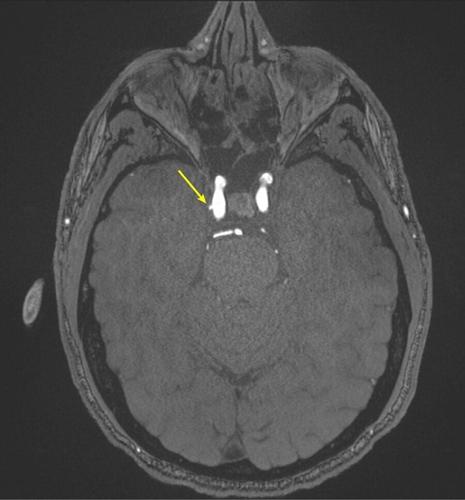

Representative axial time-of-flight MR angiography image in a 39-year-old male participant shows a laterally projecting intracranial aneurysm (arrow) originating from the right cavernous segment of the internal carotid artery. (RSNA via SWNS)